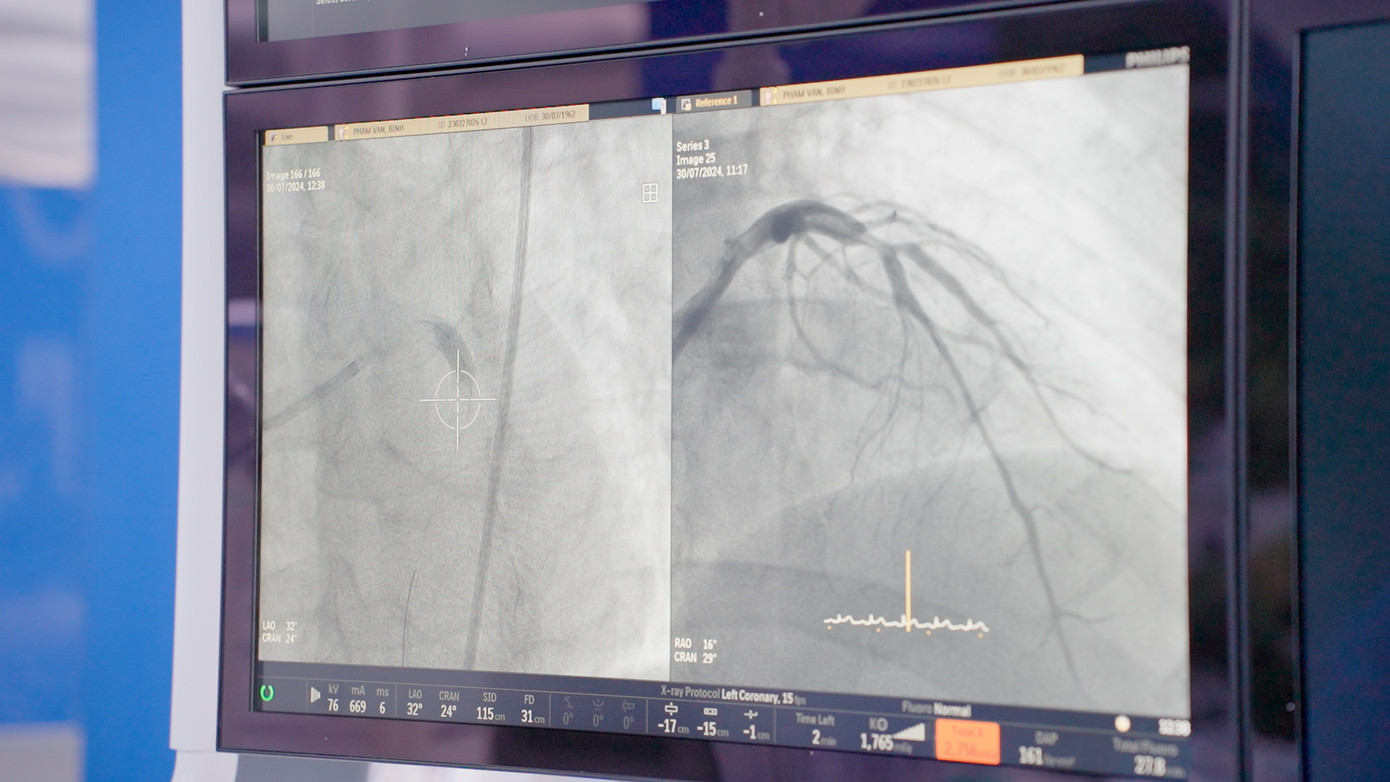

![]() |

| Tình trạng hẹp mạch vành của bệnh nhân được đo trên phần mềm vFFR |

Với việc cung cấp các hình ảnh chụp mạch vành và huyết áp, phần mềm vFFR sẽ tái tạo mô hình 3D của các động mạch này. Sau đó tự động phân tích phân tích lưu lượng dòng máu qua các đoạn hẹp của động mạch vành dưới dạng báo cáo các chỉ số chi tiết để hiển thị trên màn hình. Từ đó giúp bác sĩ có dữ liệu đánh giá đầy đủ, toàn diện để đưa ra phương án điều trị tối ưu nhất.